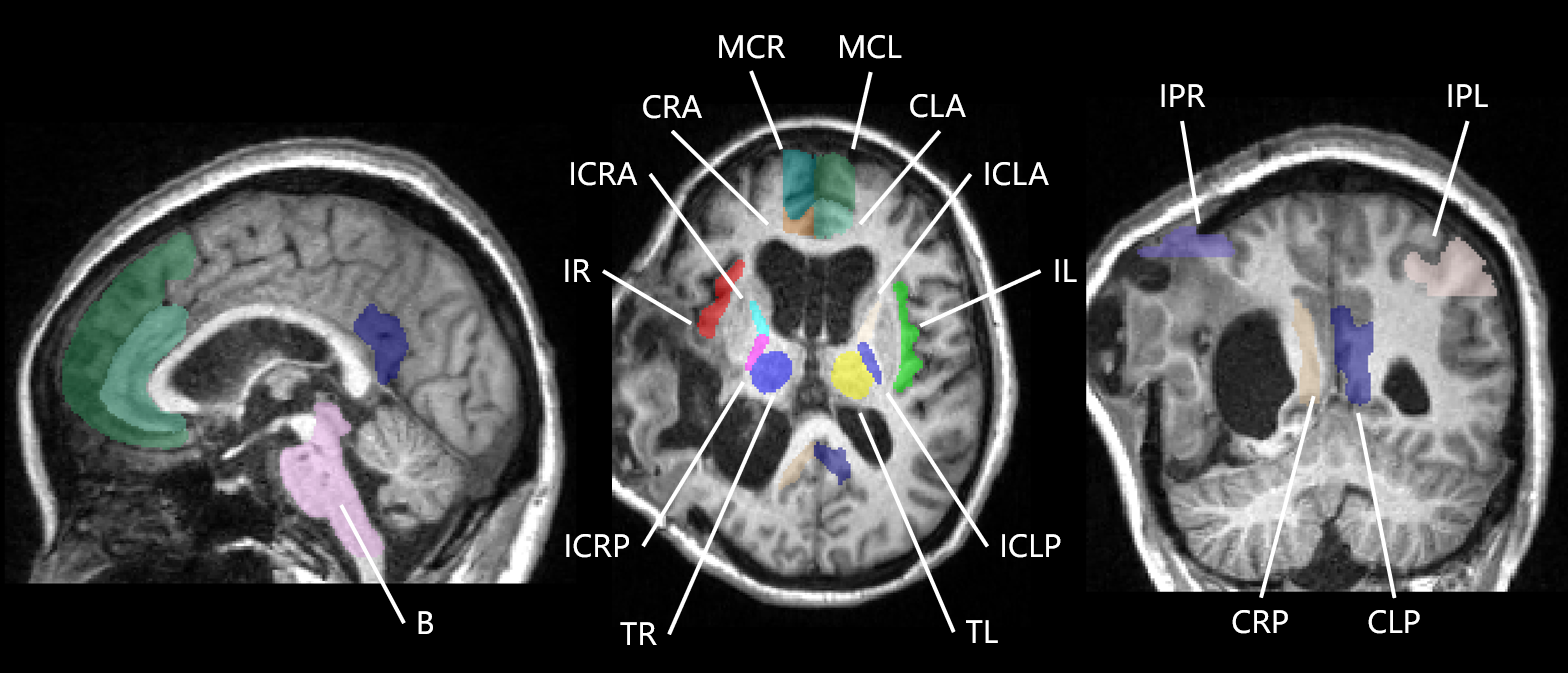

Traumatic Brain MR

Here is the illustration of the MR image and its consciousness-related brain regions of a sTBI patient. Compared with normal brain scans, brain segmentation of sTBI brain scans are affected by lesions and deformed skulls, which leads to deteriorated performance. In addition, manual labeling of these brain regions in sTBI MR scans could be laborious, and thus available annotations are extremly scarce.